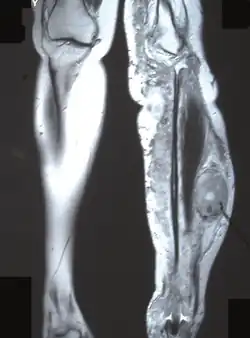

Imagen de resonancia magnética que muestra un tumor maligno de la vaina del nervio periférico en la tibia izquierda en la neurofibromatosis tipo 1.